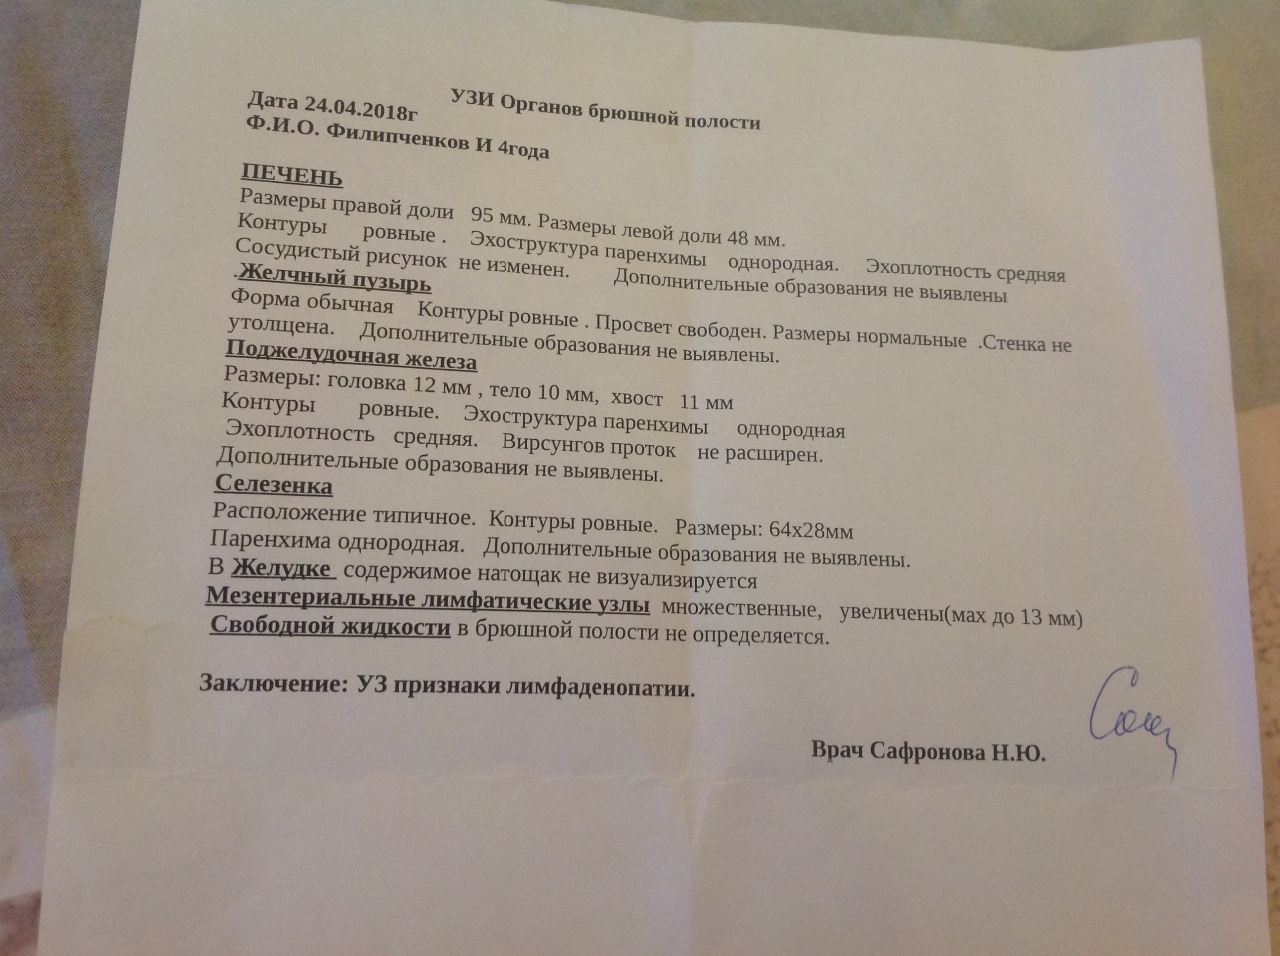

Мезентериальные лимфатические узлы: УЗИ и диагностика